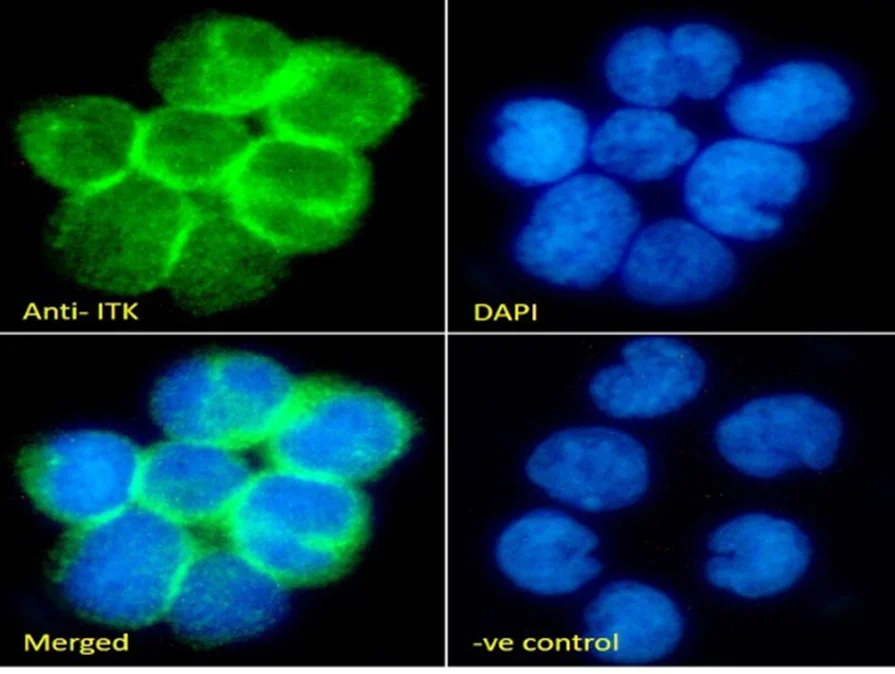

| EB05117 | Goat Anti-ITK Antibody | Pep-ELISA, WB, IF | Human, Mouse | 100µg/200µl |

| EB08802 | Goat Anti-ITK Antibody | Pep-ELISA, WB, IHC, IF, FC | Human, Rat, Cow | 100µg/200µl |